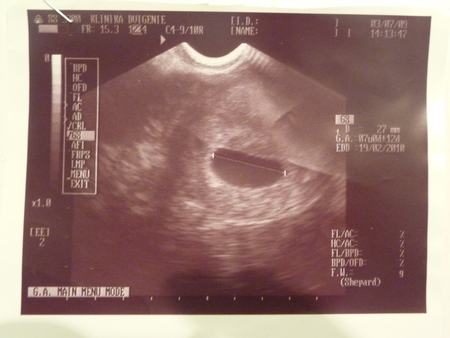

вот такими мы родились

. Тут он 27 мм, такой маленький......